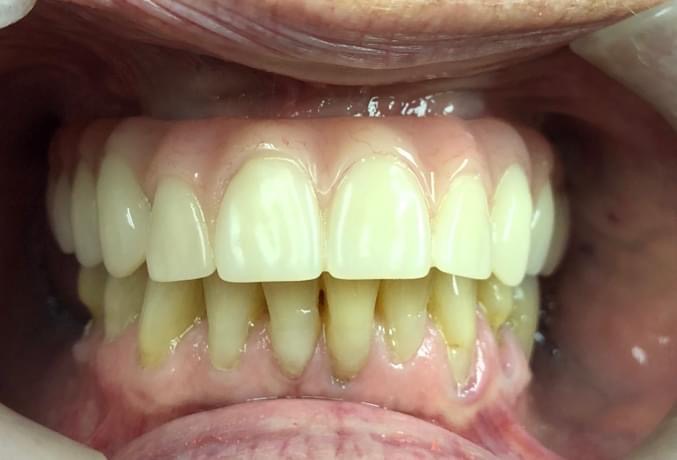

Single Implant Replacing two missing front teeth:

Single Implants replacing two Front teeth